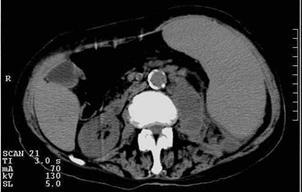

Рис. 6.18. Компьютерная томограмма брюшной полости на уровне L2. Левая почка деформирована с наличием псевдокистозных образований. Правая почка в норме. Абсцесс левой почки. | Рис. 6.19. Компьютерная томограмма брюшной полости на уровне L3. То же наблюдение, что и на предыдущей компьютерной томограмме. Определяется распространение абсцесса левой почки книзу в парааортальной области слева в виде объемного образования неоднородной плотности. |

Рис. 6.18. Компьютерная томограмма брюшной полости на уровне L2. Левая почка деформирована с наличием псевдокистозных образований. Правая почка в норме. Абсцесс левой почки.

Рис. 6.19. Компьютерная томограмма брюшной полости на уровне L3. То же наблюдение, что и на предыдущей компьютерной томограмме. Определяется распространение абсцесса левой почки книзу в парааортальной области слева в виде объемного образования неоднородной плотности.